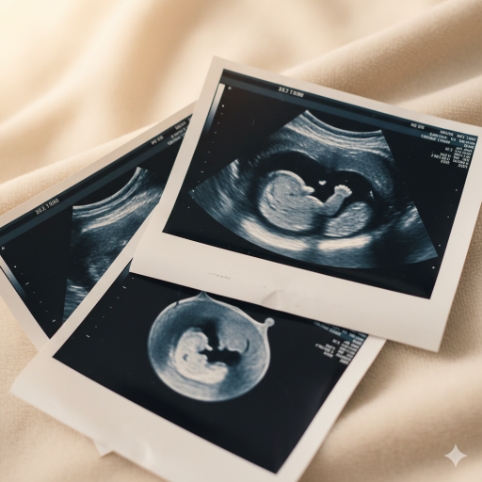

お腹の中の子どもの成長を見られるエコー写真は、妊娠期間中の大切な宝物ですよね。しかし、その写真、実は時間が経つと消えてしまう可能性があることをご存知でしたか?せっかくの思い出が色褪せてしまう前に、未来まで残る素敵なフォトブックを作成しましょう。このコラムでは、エコー写真をキレイなまま保存し、かけがえのない成長記録として残していくための具体的な方法や、愛情をたっぷり詰め込んだフォトブック作りのアイデアをご紹介します。

妊婦健診のたびに少しずつ増えていくエコー写真。小さな命が宿っていることを実感し、パートナーや家族とその成長を喜び合う、かけがえのない瞬間ですよね。母子健康手帳にそっと挟み、何度も眺めては愛おしい気持ちで胸がいっぱいになる、そんな方も多いのではないでしょうか。

一般的に、妊婦健診は出産までに14回ほど行われ、その都度エコー写真をもらえるとすると、手元には10枚から20枚ほどの写真が集まることになります。この一枚一枚が、子どもの成長の貴重な証です。しかし、この感動的な記録が、数年後には見えなくなってしまうかもしれない、と考えたことはありますか?